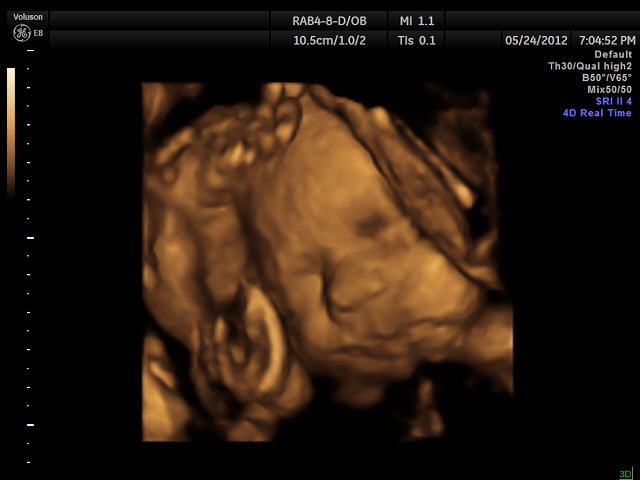

Skylar's pictures

We decided that since we did the 3D-4D ultrasound with Jeffrey that we were going to do it with Skylar as well. Well last night was the big 3D-4D ultrasound! I think it is totally amazing in so many ways. I love to be able to see and hear the baby! Here are some of her pics, but there were a little difficult to get good ones as you can tell in the pictures her leg and hand were up by her face as she was playing shy girl!!!